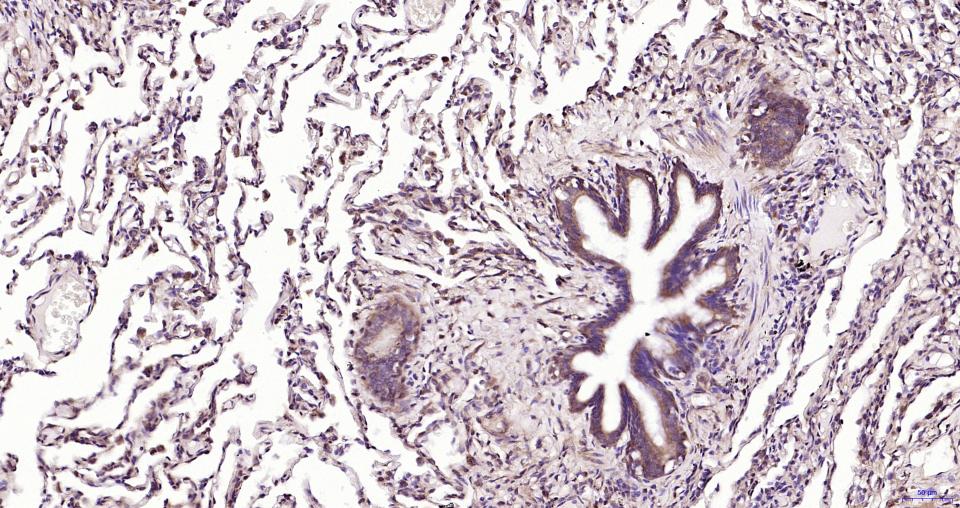

Paraformaldehyde-fixed, paraffin embedded Human Lung ; Antigen retrieval by boiling in sodium citrate buffer (pH6.0) for 15 min; Antibody incubation with MyD88 Monoclonal Antibody, Unconjugated(bsm-61269R) at 1:200 overnight at 4°C, followed by conjugation to the SP Kit(Rabbit, SP-0023) and DAB (C-0010) staining.